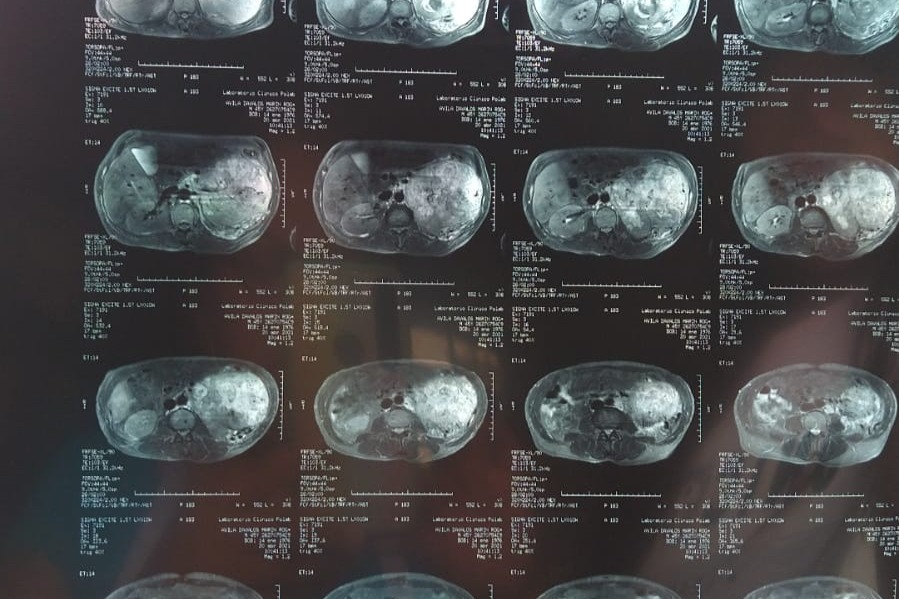

I never thought to do this but today I find myself in a very difficult situation. I want to be able to help my parents but I can't by myself. That is why my family and I ask for your help from the bottom of our hearts. My 55-year-old father with DM2 SAH (Type 2 Diabetes Mellitus and Hypertension) detected a large tumor two weeks ago that has been growing for many years. Known as Left Renal CA (Kidney Cancer) DX. My family and I have been going through very difficult times these past weeks since unfortunately we lost my Grandmother last month on April 14, 2021. A few weeks later we found out about the tumor that had been developing and forming in his body. Thanks to a fall he had and from which he began to shed blood, we decided to have him checked out because almost two years ago he had surgery to remove a hernia he had. When taking him to the clinic the Doctors decided to take tests to see what was going on in which his tumor was detected. Given the circumstances that we have gone through, my mother with the loss of my grandmother began to feel bad. So we also decided to take her to the doctor for a medical check-up in which they have also given us bad news since they have detected the development of a tumor in her throat and she also has symptoms of Diabetes. We are going through a very difficult and painful situation mentally and physically. We have had many medical expenses and there are many more expenses to come that we cannot afford like the surgery that my dad is going to need and the medical expenses that he and my mom will be faceing . We have seen several specialists with different opinions. But thank God we have found a doctor to operate on him on Monday May 10th, 2021. My family is a low-income family. That is why we are asking for your help to raise funds with all the medical expenses that my mom and dad will need. We have Faith in God and with the help of good people with you helping us with your prayers and donations we will be able to get through this difficult situation. Thank you very much and may GOD bless you and multiply you in every way.

Nunca pensé en hacer esto, pero hoy me encuentro en una situación muy difícil. Quiero poder ayudar a mis padres pero no puedo por mí misma. Es por eso que mi familia y yo pedimos su ayuda desde el fondo de nuestro corazón. Mi padre de 55 años con DM2 HAS (diabetes mellitus tipo 2 e hipertensión) detectó hace dos semanas un gran tumor que ha estado creciendo durante muchos años. Conocido como CA renal izquierdo (cáncer de riñón) DX. Mi familia y yo hemos pasado por momentos muy difíciles estas últimas semanas desde que lamentablemente perdimos a mi abuela el 14 de abril del 2021 el mes pasado. Unas semanas después nos enteramos del tumor que se había estado desarrollando y formándose en el cuerpo de mi papá. Gracias a una caída que tuvo y de la que empezó a derramar sangre, decidimos hacer que lo revisaran porque hace casi dos años lo operaron para extirpar una hernia que tenía. Al llevarlo a la clínica los médicos decidieron hacerle pruebas para ver qué estaba pasando en el que se detectó su tumor. Dadas las circunstancias por las que hemos pasado, mi madre con la pérdida de mi abuela empezó a sentirse mal. Así que también decidimos llevarla al médico para un chequeo médico en el que también nos han dado una mala noticia ya que han detectado el desarrollo de un tumor en su garganta y también tiene síntomas de Diabetes. Estamos atravesando una situación muy difícil y dolorosa mental y físicamente. Hemos tenido muchos gastos médicos y hay muchos más gastos por venir que no podemos afrontar, como la cirugía que va a necesitar mi papá y los gastos médicos que él y mi mamá tendrán que afrontar. Hemos visto a varios especialistas con opiniones diferentes. Pero gracias a Dios hemos encontrado un médico para operarlo el dia Lunes 10 de Mayo 2021. Mi familia es una familia de bajos ingresos. Por eso les pedimos su ayuda para recaudar fondos con todos los gastos médicos que necesitarán mi mamá y mi papá. Tenemos Fe en Dios y con la ayuda de buenas personas cono usted en ayudándonos con tus oraciones y donaciones podremos superar esta difícil situación. Muchas gracias y que DIOS te bendiga y te multiplique en todos los sentidos.